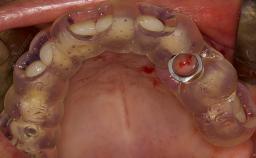

Complications of Sinus Floor Elevation

Sinus floor elevation using either the lateral window or transcrestal approach is a predictable surgical procedure with proven success, low complication rates, and high survival rates.

However, as with all surgical procedures, complications and failures do occur.

This learning module will provide an overview of the most commonly seen intraoperative and postoperative complications associated with sinus floor elevation and will discuss management in terms of preventative measures as well as treatment strategies.